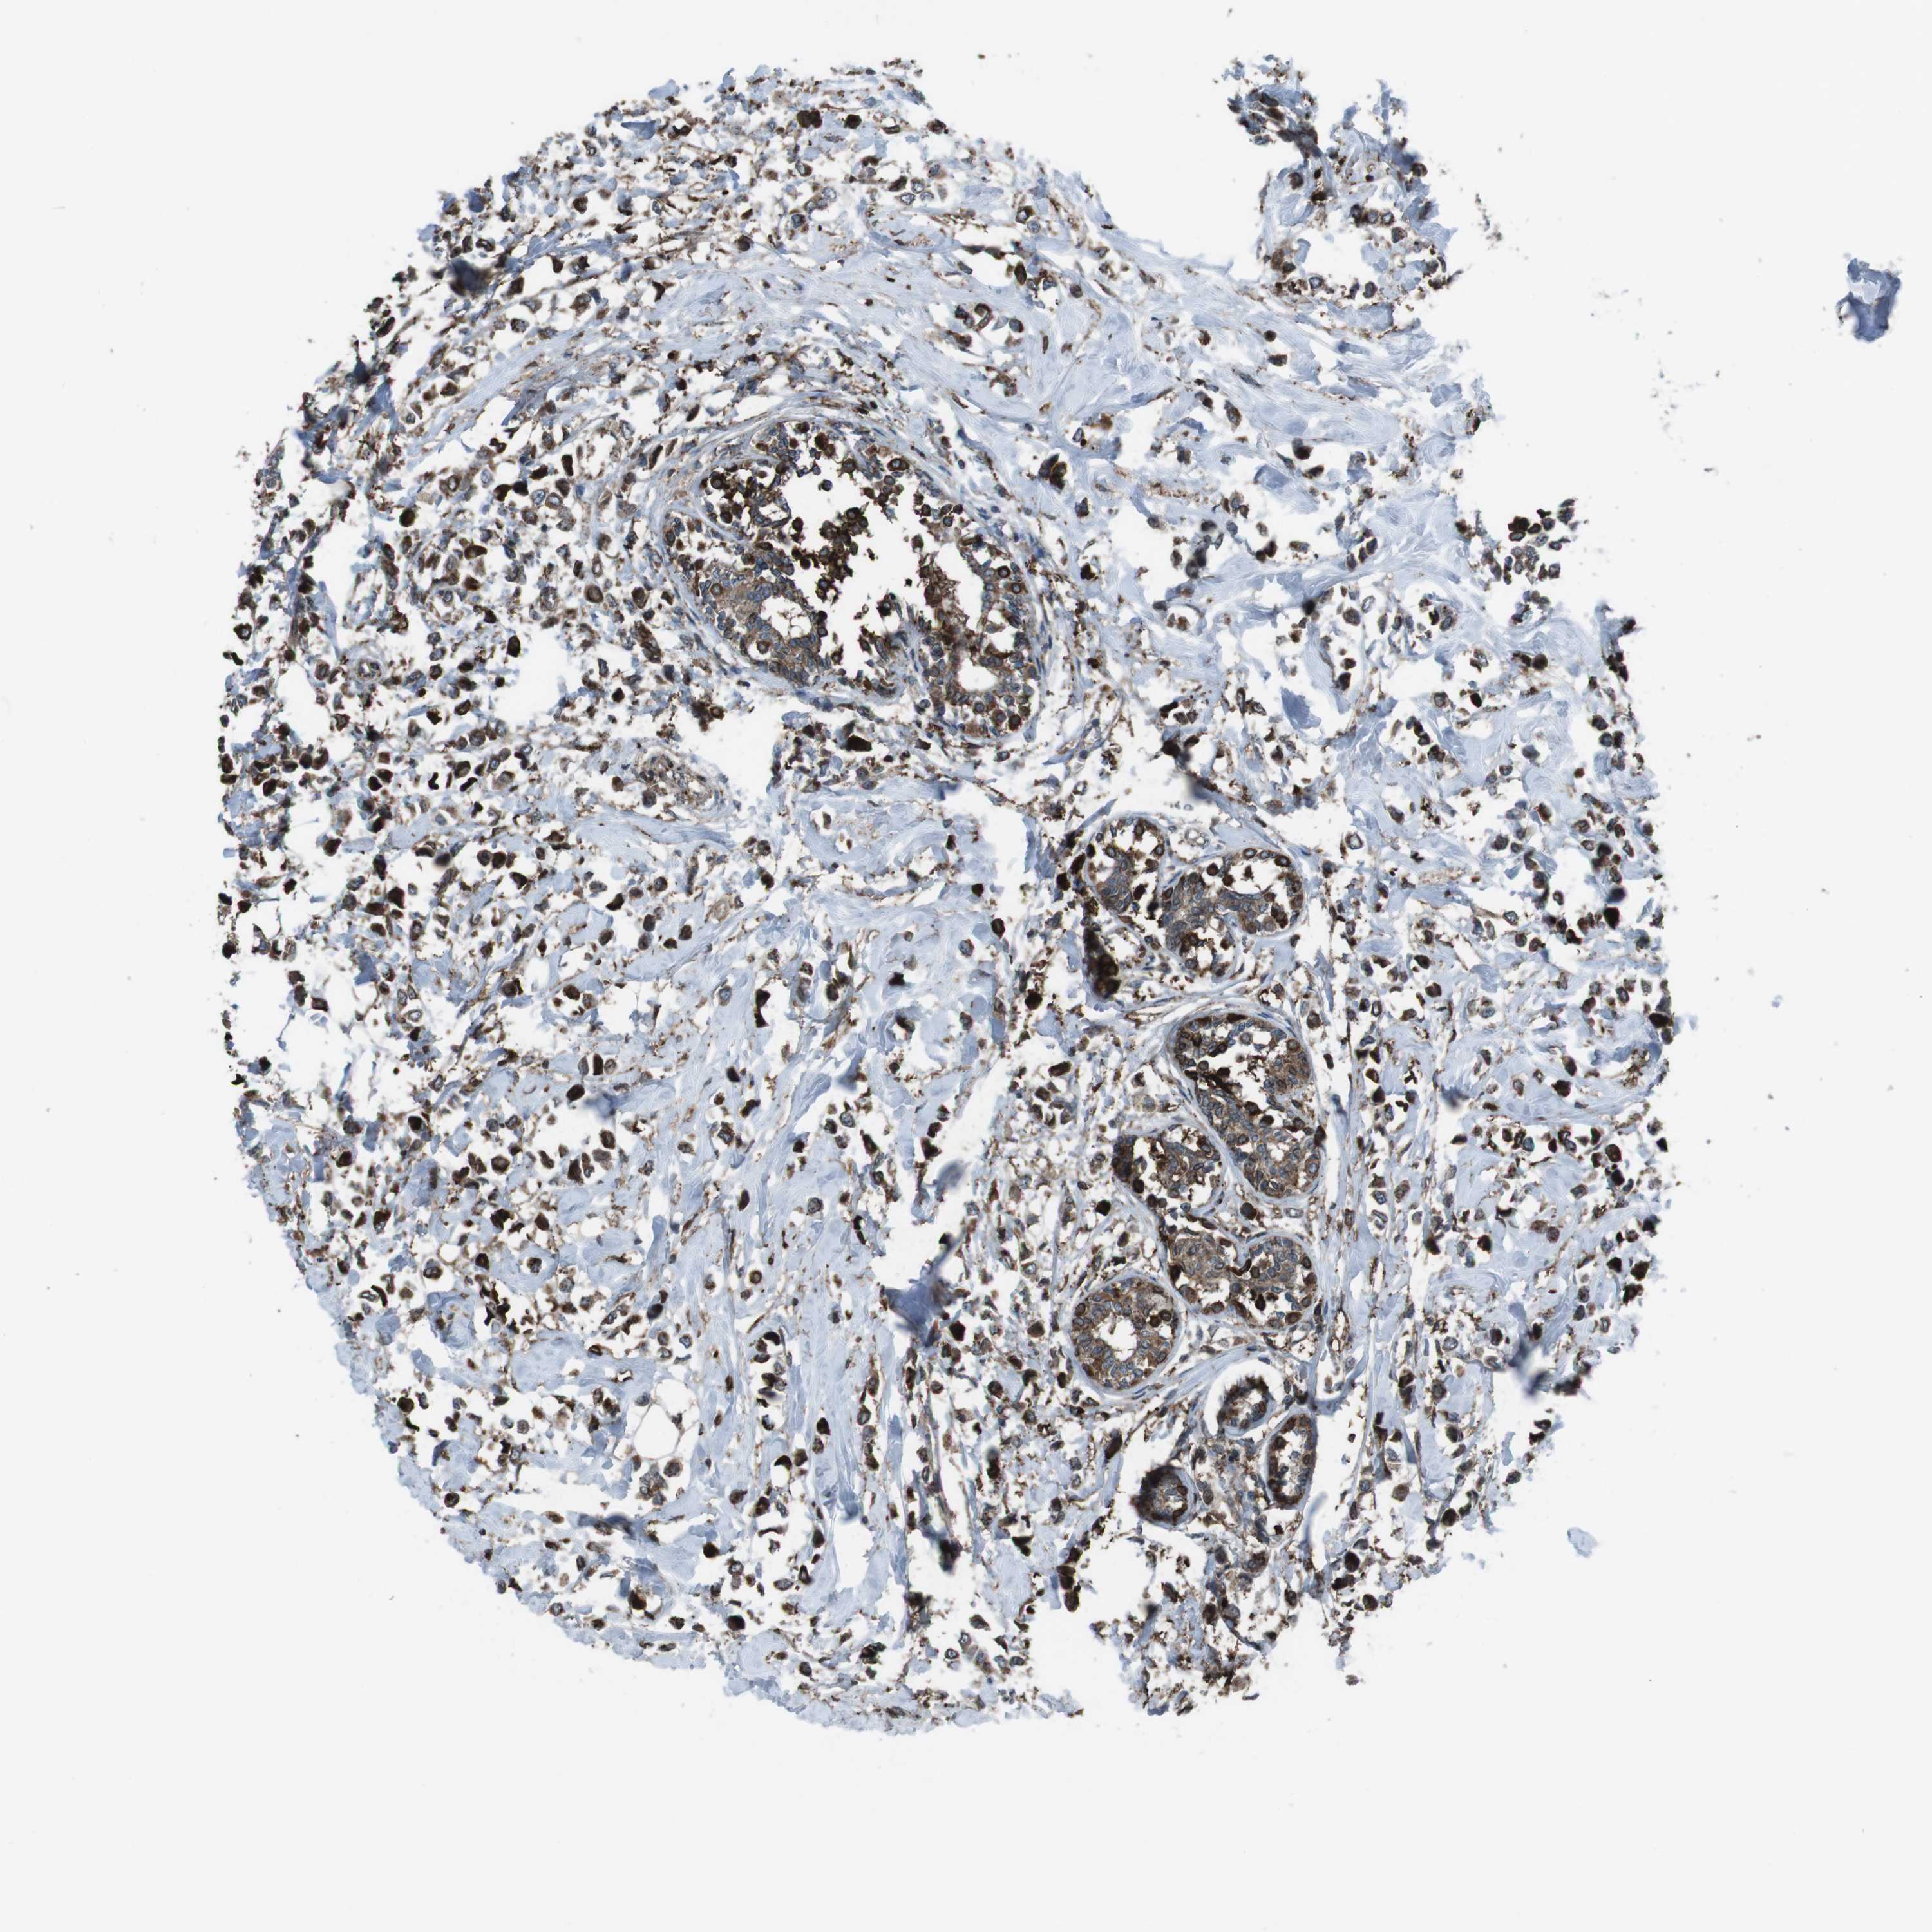

CANCER BREAST CANCER Show tissue menu

BRCA TCGA BRCA VALIDATION PROTEIN EXPRESSION

Breast cancer

Human cancer

GDF10 is not prognostic in Breast Invasive Carcinoma (TCGA)